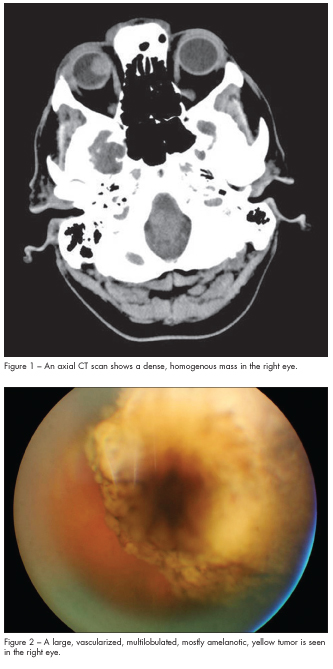

A 53-year-old man presents for evaluation of an intraocular mass in his right eye. One month earlier he had tripped over a space heater and hit his forehead on a countertop. At that time he was treated in an urgent care clinic for a laceration on his left forehead. Because he had a persistent chronic headache after his head trauma, he followed up with his family physician. The physician ordered a CT scan of the head, which revealed a large, dense, homogenous mass in the right eye (Figure 1).

A slit lamp evaluation is unremarkable as is a dilated fundus examination of the left eye. Funduscopic examination of the right eye reveals pigmented cells in the vitreous and a large, vascularized, multilobulated yellowish tumor involving the superonasal quadrant of the retina (Figure 2). A B-scan ultrasound shows a well-circumscribed homogenous tumor measuring 18 mm 3 15 mm (basal dimensions) and a height of 12 mm (Figure 3).